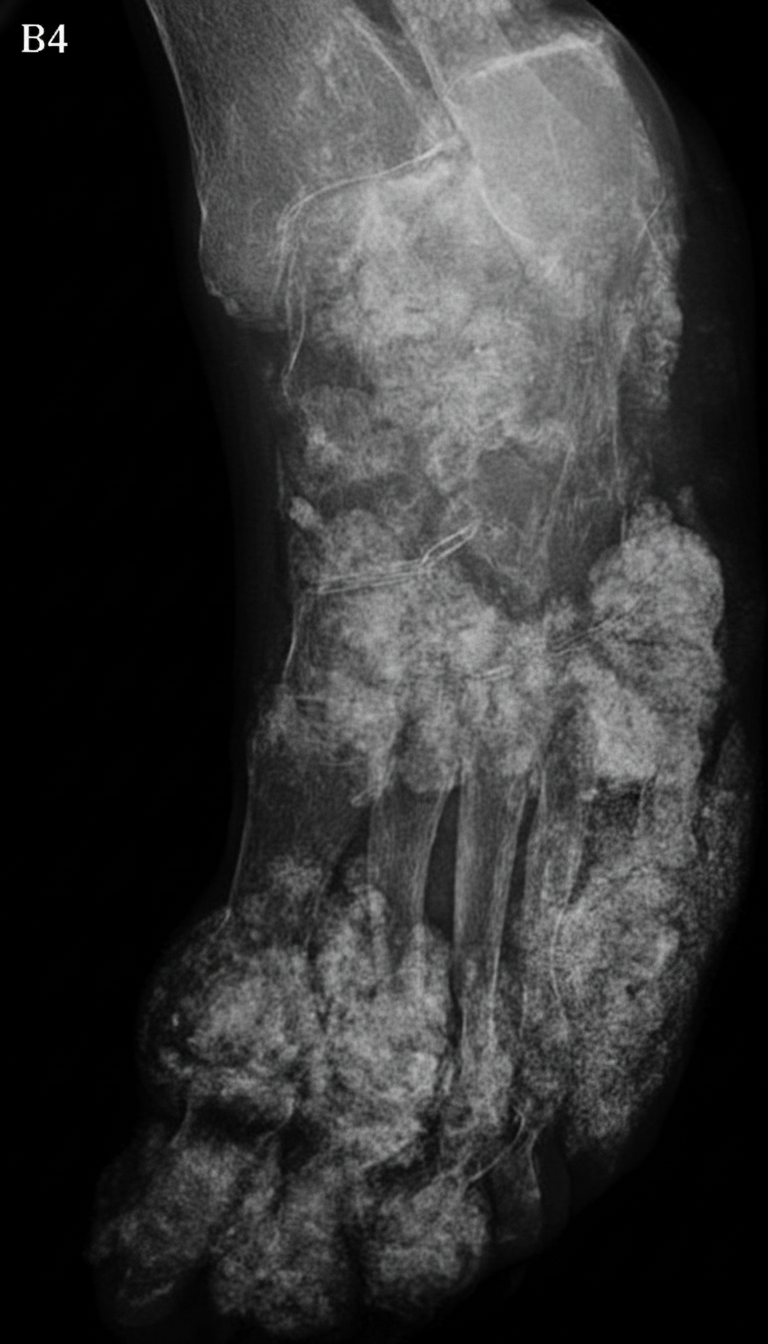

Explanation: ***Gout*** - Classic **punched-out erosions** with **overhanging edges** on imaging are pathognomonic for gout, particularly when involving the **first metatarsophalangeal joint**. - Presence of **tophi** (urate crystal deposits) and predilection for the **great toe** are characteristic radiological and clinical features of chronic gout. *Osteomyelitis* - Would show **bone destruction** with **sequestrum formation** and surrounding **soft tissue swelling** on imaging. - Typically associated with **systemic signs** like fever and elevated inflammatory markers, unlike the localized joint changes seen in gout. *Vasculitis* - Primarily affects **blood vessels** causing ischemic changes rather than the specific **joint erosions** seen in this case. - Would present with **systemic symptoms** like skin lesions, organ involvement, and elevated inflammatory markers rather than localized joint pathology. *Rheumatoid Arthritis* - Shows **symmetric polyarticular** involvement with **marginal erosions** and **joint space narrowing**. - Lacks the characteristic **punched-out lesions with overhanging edges** and typically spares the **distal interphalangeal joints** unlike gout's predilection for the first MTP joint.